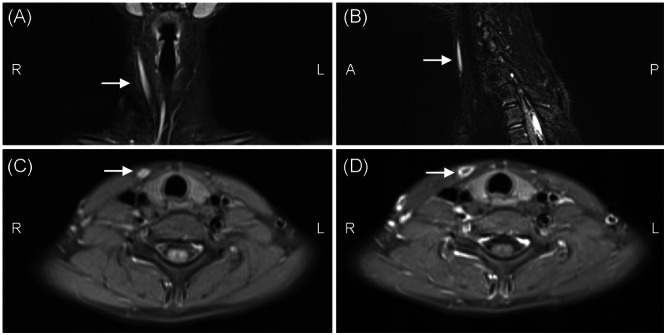

Objectives: Traditional resection of second branchial cleft fistulas (SBCFs) involves a transcervical incision in the neck, which leaves a prominent scar; therefore, endoscope-assisted excision of SBCFs through the anterior chest approach has been proposed. To introduce endoscope-assisted excision of SBCFs via the anterior chest approach and to evaluate its feasibility, validity, safety, and clinical results.

Methods: This was a study of four patients with SBCFs who underwent surgical resection with the assistance of endoscopy via the anterior chest approach between May 2012 and May 2018.

Results: All procedures were successfully performed with endoscope-assisted surgery via the anterior chest approach. The volume of blood loss ranged from 5 to 10 mL (median 6 ml). The operating time ranged from 45 to 67 min (median 50 min). No patients presented evidence of long-term complications or recurrence during the median follow-up period of 72-144 months (median 99 months). All patients were satisfied with the cosmetic outcomes.

Conclusions: Endoscope-assisted resection of SBCFs via the anterior chest approach is feasible, effective, and safe and has better esthetic effects. Therefore, SBCF surgery via the anterior chest approach could be a novel and superior treatment option for patients with SBCFs.